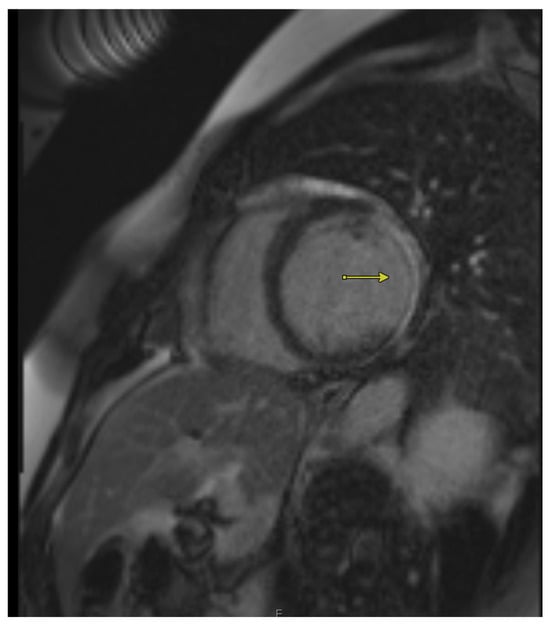

3. Cardiac Magnetic Resonance Imaging (CMR)

3.1. Quantification of Transmural Infarction to Determine Viability

3.2. Role of CMR in Quantifying Wall Thickness to Assess Viability